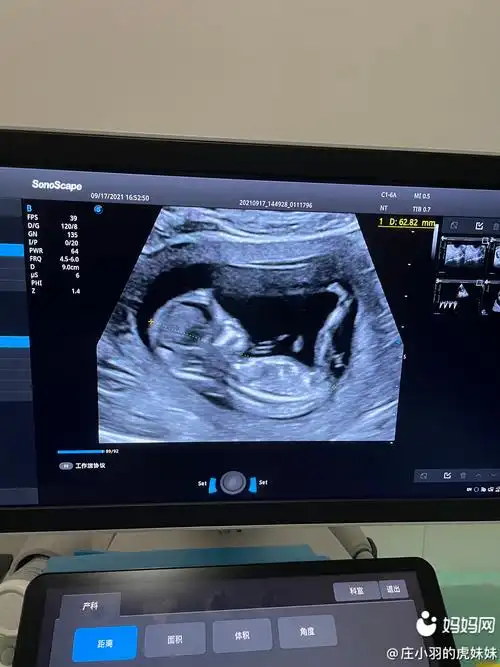

nt通过啦!有伙伴会看男女嘛

nt图像上有三个点是怀女孩的概率更高吗?

13周已生男宝nt单子数据分享,原来看三个亮点就知男孩女孩 - 柚鼠知识

已生女儿 nt 最明显的女宝特征看数据